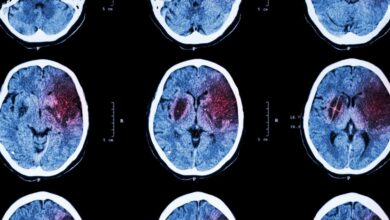

دارویی که میتواند به توانبخشی پس از سکته مغزی کمک کند

بررسی جدید پژوهشگران “دانشگاه ایالتی اوهایو” نشان میدهد که یکی از داروهای اختلال عصبی میتواند به توانبخشی پس از سکته…